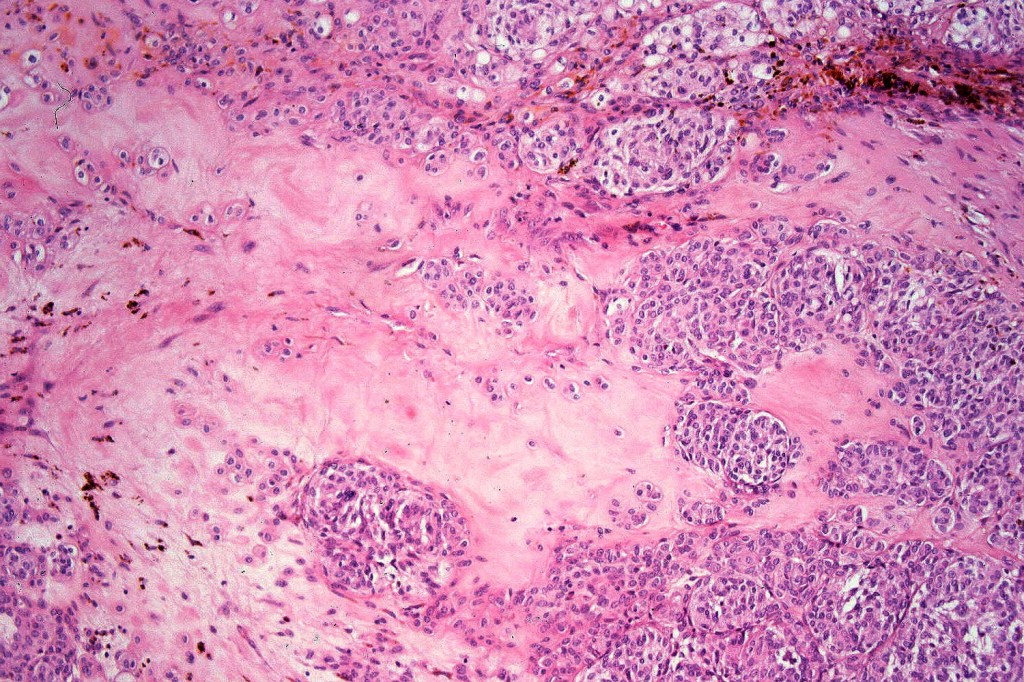

Atpical blue nevus

This is exceedingly rare and the diagnosis should be used very sparingly. It is likely quite benign although very occasionally, a sentinel node biopsy is positive. Great care must be taken to make sure that a blue nevus-like melanoma isn’t missed. It shows the low power features of a blue nevus but high power scrutiny reaveals pleomorphism, nuclear hyperchromatism and increased mitotic activiy (<1 sq mm). Abnormal mitoses are absent as is necrosis. Perineural involvement can be seen but lymphovascular invasion is absent.